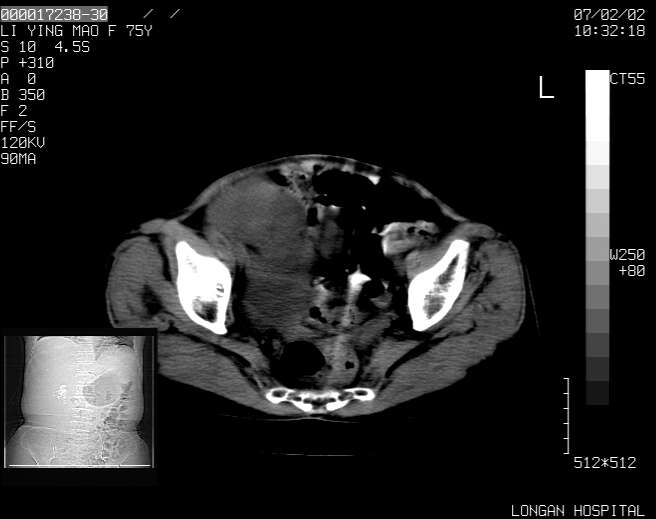

以下是引用dyqct在2007-2-10 8:53:00的发言:[br]考虑:1、肝脏多发囊肿[br] 2、左肾囊肿,右肾多发结石并积水。[br] 3、右胸少量积液。[br] 4、右肾周包裹性积液或淋巴管瘤(有见缝就钻的征象、薄隔、小结节状钙化)?[br] 5、腰椎动脉瘤样骨囊肿?[br] [br] [br]